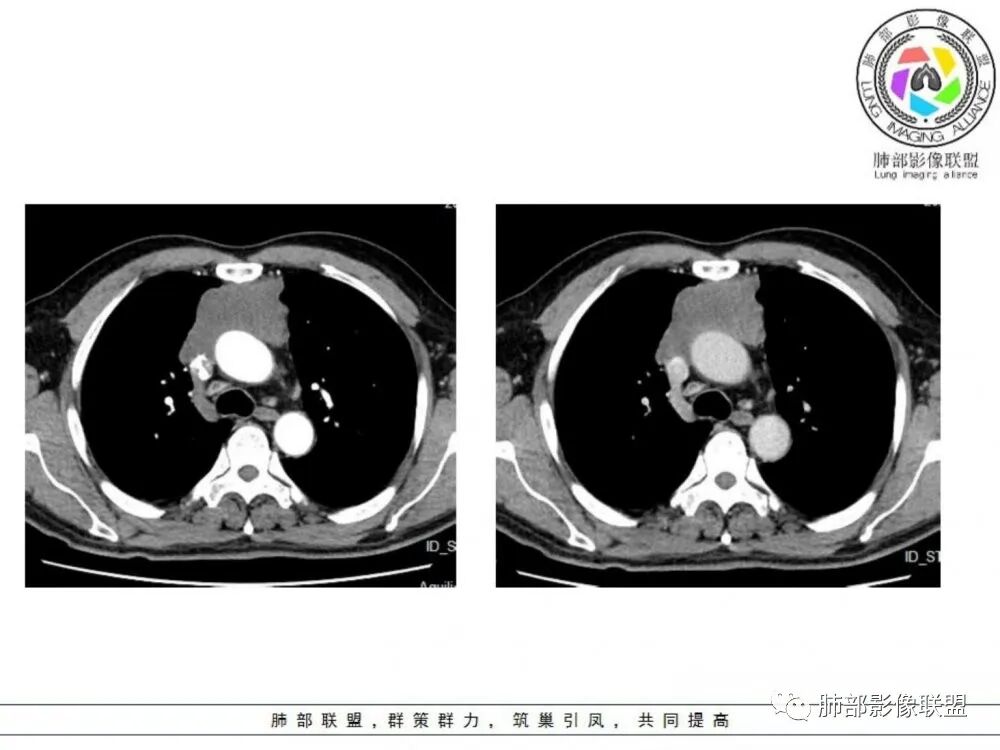

男性患者,65岁,前胸后背疼痛一个月。影像学前上纵隔分叶状的软组织肿块,肿块形态怪异,偏软,位于大血管间隙前,并有向血管后间隙发展的趋势,平扫CT值为40左右,增强扫描中心部未见强化,周围轻度的强化,约为50左右。前上纵隔的疾病谱包抬胸廓内甲状腺肿、胸腺瘤/癌、畸胎瘤、淋巴瘤。少见的心包囊肿或支气管囊肿。根据肿块的形态及强化特点,首先还是排除了胸内甲状腺肿及胸腺来源的肿物,这类的肿物强化比较明显。畸胎瘤成分比较复杂,具有软组织钙化或者脂肪类的组织,这个肿物虽然在平扫的时候好像有斑点状的钙化灶,但是总体成分还是比较单一,所以还是排除畸胎瘤的诊断。所以这样的情况是考虑:淋巴类的肿瘤,注意排除心包的囊肿或支气管来源的囊肿。

临床,老年男性,病史一月。1 定位,骑跨大血管,大部分位于胸腺区域内,周边部分胸腺脂肪有混浑浊,起源于胸腺区的组织应该没有问题。2 定性 。恶性征像,分叶,大血管侵润,pet高代谢,左侧庄层胸膜增厚(类似脑膜瘤的脑膜尾征,良性表现?)。良性征像,病灶均匀,无明确坏死?综合恶性征像多些,考虑恶性可能大。病灶分两部分,部分层面似有明确分割,两个性质的病灶长一块,还是,一个病灶两种不同成分?一个病灶伴均匀坏死?CT值41hu,坏死好像高了点,一个病灶,相同成分,只是血管分布不同,增强是持续流入型强化。纤维类?编不下去了,岔路太多,祭出法宝按概率蒙吧:侵袭性胸腺瘤>神经纤维瘤>乏血供CD

老年男性,前纵隔不规则软组织肿块影,密度欠均匀,与大血管分界欠清,上腔静脉局部包绕受侵,增强扫描不均匀轻度强化,PET-CT高代谢。考虑恶性肿瘤性病变,胸腺癌可能。鉴别淋巴瘤。

男性患者,65岁,前胸后背疼痛一个月。胸部影像:前上纵隔分叶状的软组织肿块,形态不规则,包绕大血管生长趋势,与周围分界不清,密度较均匀,呈多结节融合,肿块周围可见肿大淋巴结,内乳动脉旁淋巴结大,上腔受累,肿物内可见低密度区,增强扫描周围轻度强化。考虑:恶性病变,淋巴瘤?胸腺神经内分泌肿瘤?鉴别胸腺瘤

中老年男性,前纵隔占位,基本居中,向两侧生长;边缘膨隆分叶,部分边界不清,增强不均匀轻中度强化,坏死区边界不清;周围多发增大淋巴结,考虑恶性。主要在胸腺癌、胸腺瘤、淋巴瘤之间鉴别。病灶偏软,有钻缝样生长,这些征象偏向于淋巴瘤。但此例老年患者,病灶内有点状钙化,缺乏结节堆砌感,倾向胸腺癌诊断。